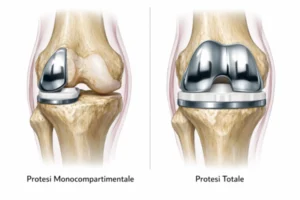

Introduzione: La protesi monocompartimentale di ginocchio (Unicompartmental Knee Arthroplasty, UKA) è una procedura efficace nel trattamento dell’artrosi limitata a un compartimento, con vantaggi potenziali rispetto alla TKA in termini di recupero funzionale, preservazione ossea e cinematica più fisiologica. Il successo è fortemente dipendente dalla corretta selezione del paziente e dall’esecuzione tecnica.

La UKA nasce come soluzione per pazienti con artrosi confinata a un compartimento (più frequentemente il mediale), con l’obiettivo di sostituire solo la parte malata preservando osso, legamenti e parte della cinematica nativa. Rispetto alla TKA, è associata (in pazienti ben selezionati) a minore invasività, recupero più rapido, migliore propriocezione e maggiore “sensazione di ginocchio naturale”. Tuttavia presenta un profilo di fallimento più sensibile a errori di indicazione e tecnica, e richiede criteri di selezione rigorosi.

UKA vs TKA

A parità di corretta indicazione, l’UKA resta una procedura con risultati eccellenti nei “best responders”, ma con un profilo di fallimento più sensibile a variabili tecniche e di sistema (esperienza/volume). Per questo è utile distinguere i determinanti dell’outcome in fattori legati al paziente, all’impianto, all’esecuzione chirurgica e all’organizzazione.